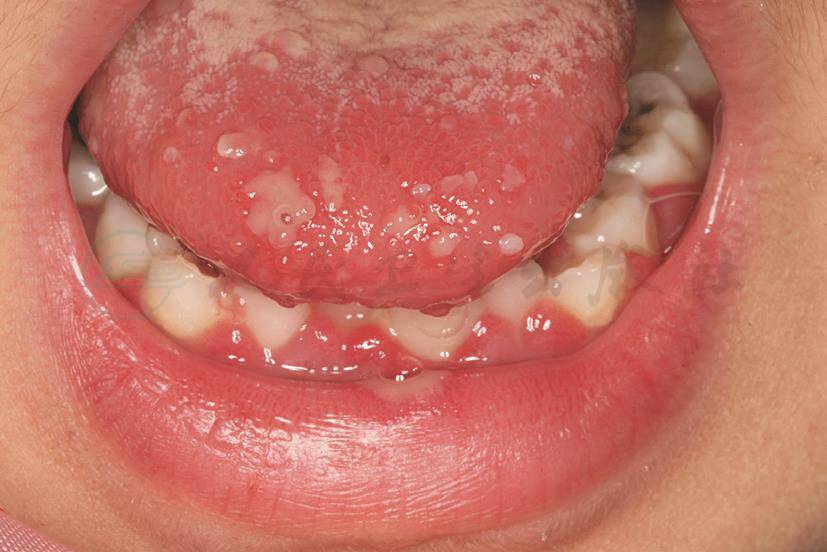

舌背、下唇、双颊成簇水疱及糜烂,部分融合成片,形状不规则,上覆假膜,周围黏膜充血,全口牙龈充血肿胀(图1)。

图1 原发性疱疹性龈口炎

舌背、下唇糜烂,下颌牙龈红肿(武汉大学口腔医学院供图)